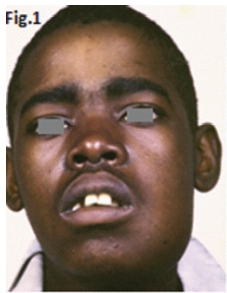

This 22 year old male patient (Figs.1 & 2) presented with a slow growing swelling in the left mandibular molar region. Figures 3, 4, 5 & 6 are images of three other patients with the same condition. Discuss the radiological features and what is your diagnosis?

Fig 1 & 2: the large lesion of left mandible shows a honeycomb-like distribution of calcifications. The borders are corticated. The tumour has displaced the mandibular molar tooth. A histological diagnosis of calcifying epithelial odontogenic tumour (Pindborg Tumour) was made. Fig.3 shows a Pindborg tumour distal to left second premolar associated with displacement of the first molar tooth. Fig.4 shows a similar tumour with mixed lucency-opacity between right premolar and molar teeth. Figs 5 & 6 show coronal and axial CT views of a large Pindborg tumour affecting the right maxilla. Note the marked expansion and cortical destruction. Calcifying epithelial odontogenic tumour is a rare benign neoplasm, accounting for less than 1% of all odontogenic tumours. The average age at diagnosis is 40 years; however, the tumour can occur at any age. It occurs equally in males and females. Approximately two thirds of cases are reported to occur in the mandible. Most cases occur in the premolar-molar area and are commonly associated with an unerupted tooth. The tumour is a painless, slowly enlarging mass. Histologically the tumour has a very characteristic appearance. Sheets of polyhedral cells with well-defined eosinophilic cytoplasm and hyperchromatic nuclei are featured. Amyloid and ringlike calcification may also be present. The tumour may be irregular or, in some cases, the cystic lesions may be well defined and corticated, whereas others appear ill defined. Small unilocular lesions may have a completely radiolucent centre (Fig.3). Others may have variable amounts of small flecks of calcifications scattered throughout. Larger lesions have a multilocular or honeycomb appearance. The tumour can displace and often prevent the eruption of teeth. Radiologically the tumour may be very similar to the calcifying odontogenic cyst, adenomatoid odontogenic tumour and ameloblastic fibro-odontoma.